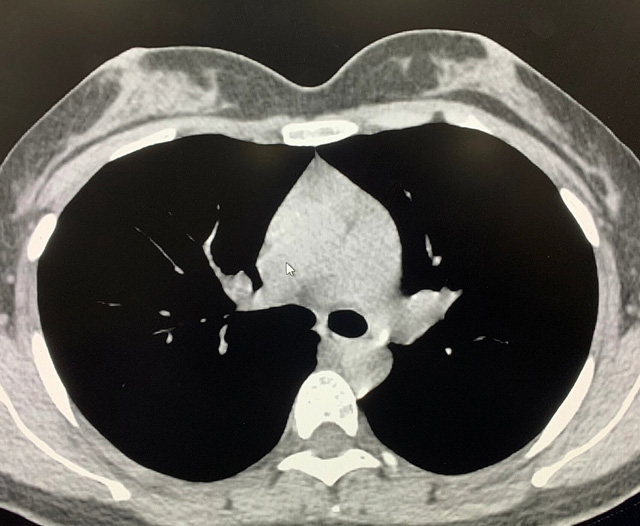

能譜純化技術CT低劑量胸部掃描

能譜純化技術的核心是通過物理濾過(如錫濾片)或軟件算法,選擇性濾除低能X射線光子,保留高能光子。在胸部低劑量CT掃描中顯著提升了圖像質量與輻射劑量的平衡。

1.明顯降低患者的輻射劑量,能譜純化後,使重疊無用的X線濾除。

2.明顯提高圖像質量,高能光子穿透力強,光子通量更均勻,圖像噪聲(標準差)可降低20%-40%。

3.能譜純化技術相比於低千伏低劑量技術,可以有效消除線性硬化偽影,提高診斷效能;

優勢輻射劑量顯著降低相較於常規CT,輻射劑量減少約70%-90%,尤其適合需多次隨訪的高危人群(如肺癌篩查),降低輻射相關癌症風險早期肺癌篩查效果明確可清晰檢測毫米級肺結節,顯著提高早期肺癌檢出率,降低死亡率。檢查快捷且普及性高單次掃描僅需數秒,無需對比劑,設備廣泛配置於基層醫院,便於大規模篩查。長期成本效益顯著雖單次費用與常規CT相近,但早期幹預可大幅降低晚期治療費用及社會醫療負擔。技術優化提升圖像質量迭代重建算法(如ASIR、MBIR)在降低劑量同時減少噪聲,平衡影像質量與安全性。